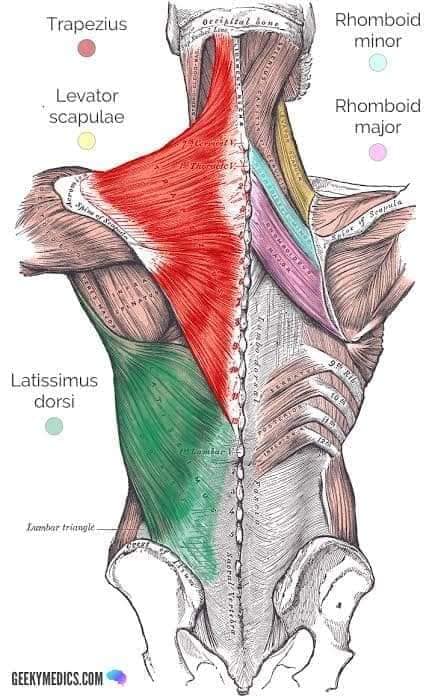

Поверхневі спинні м'язи

М'язи, що піднімають лопатку: Трапецієподібний м'яз: великий м'яз, що покриває верхню частину спини. Його функція - підтримка і рух лопаток, а також забезпечення стабільності хребта.

М'язи, що ведуть лопатку до хребта: Широкий м'яз спини: великий м'яз, що розташований в нижній частині спини. Він відповідає за рухи плечей і лопаток, а також за розширення верхньої частини тулуба.